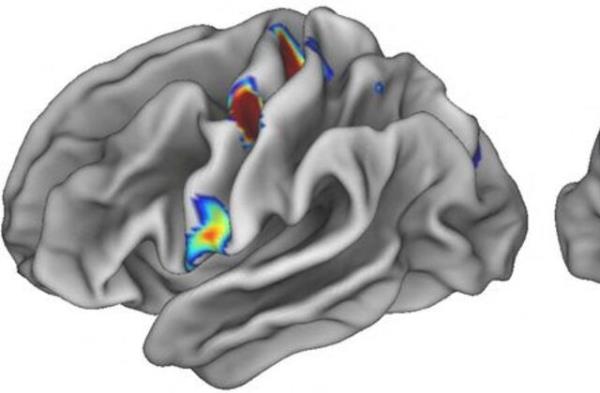

研究人员周三表示,他们发现,大脑中控制身体运动的运动皮层与一个网络有关,该网络涉及思考、计划、精神觉醒、疼痛和内脏控制,以及血压和心率等功能。

他们在运动皮层中发现了一个以前未知的系统,这个系统表现在多个节点上,这些节点位于已知负责特定身体部位(手、脚和脸)运动的大脑区域之间,当许多不同的身体运动一起进行时,这些节点就会参与其中。

研究人员将这一系统称为躯体认知行动网络(SCAN),并记录了它与大脑中帮助设定目标和计划行动的区域之间的联系。

这个网络也被发现与大脑区域相对应,正如对猴子的研究所显示的那样,大脑区域与包括胃和肾上腺在内的内脏器官相连,允许这些器官在预期执行特定动作时改变活动水平。他们说,这或许可以解释仅仅是思考一项艰巨的未来任务就会引起出汗或心率加快等身体反应。